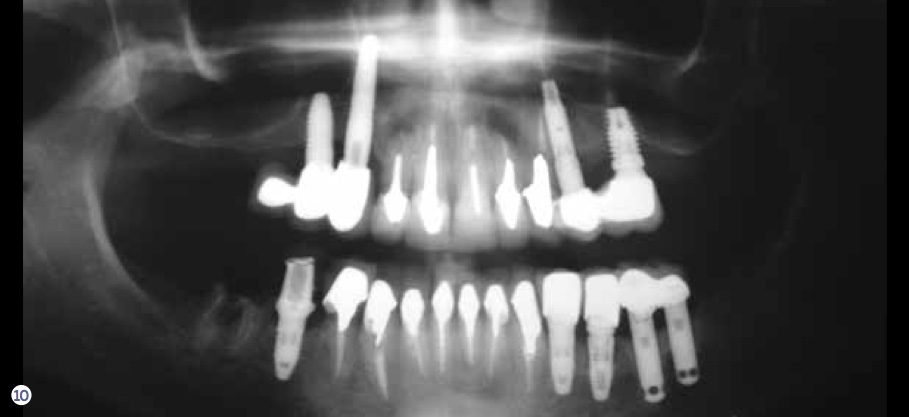

After evaluating the contingency, priority, and risk, a clinician can determine the prognosis. Because every patient presents with different risks, priorities, and contingency factors, a standard treatment plan will not work for every patient. Therefore, a customized treatment plan is necessary to develop a plan based on the patient’s CPR. For example, utilizing the CPR protocol, a segmented reconstruction can be planned for a patient—if appropriate—that consists of an implant-supported screw-retained restoration (Figure 10 through Figure 15). By combining these three assessment tools, clinicians are able to create better solutions and treatment plans for their patients.

Fig 10. Radiographic view of a heavily restored 37-year-old patient revealing numerous problems associated with the teeth and implant-supported restorations.

Figure 10